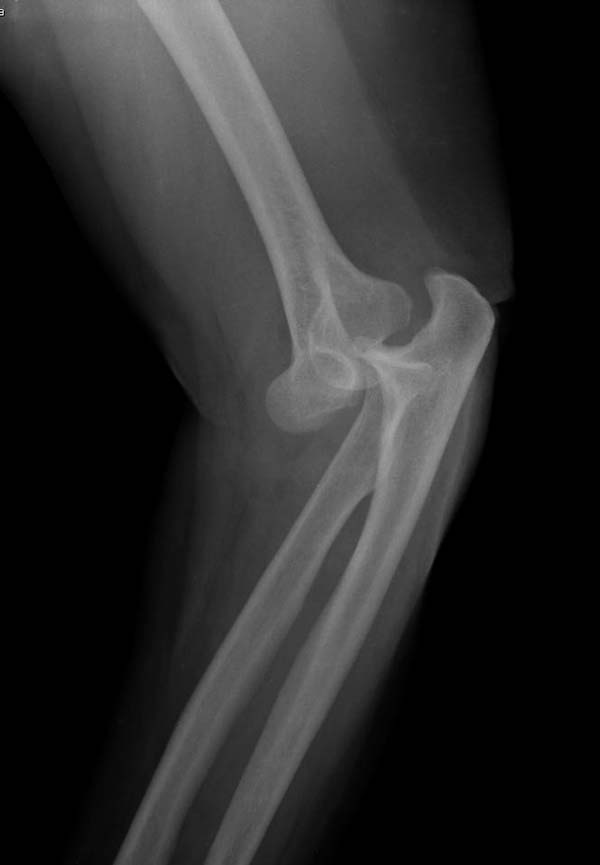

В заключение: результат применения трансартикулярной фиксации (более 20 лет) в сравнении со сложными реконструктивными операциями показывает лучшую амплитуду движений! Возможно, у коллег имеются другие варианты, а мы без привлечения больших затрат решаем проблему.

Для примера здесь случай начатый в другом центре, а потом переправленный к нам.

Снимки: 1-2 вывих, 4-5 вторичное смещение в гипсе, реконструкция латеральной связки и капсулы 13-14, повторный вывих после реконструкции, перевод в наш центр; 18-21 временная фиксация, 22-25 трансартикулярная фиксация и нестабильная головка фиксирована спицами, 29-30 амбулаторно, 32-33 после удаления винта и спиц...